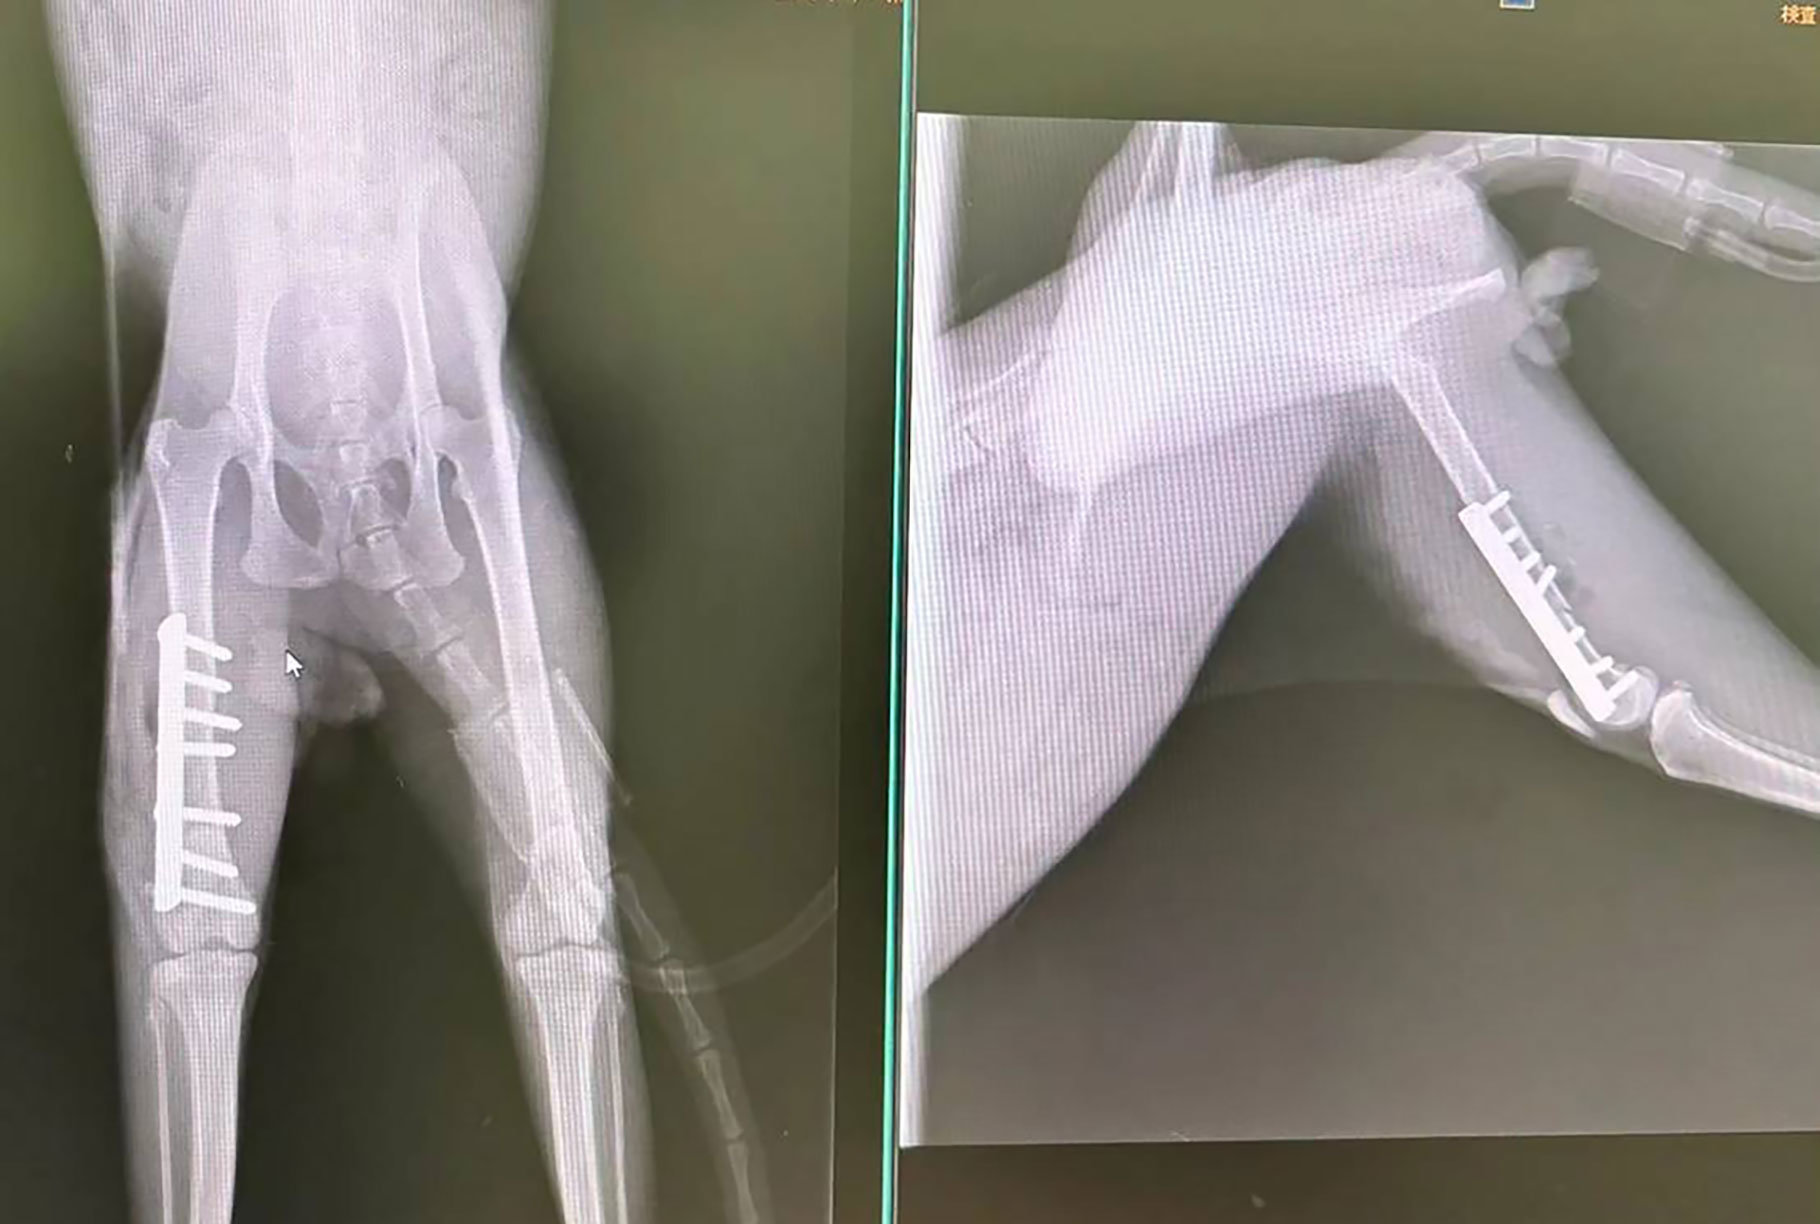

手術後のレントゲン写真です

骨折していた脚はきれいに繋がっています